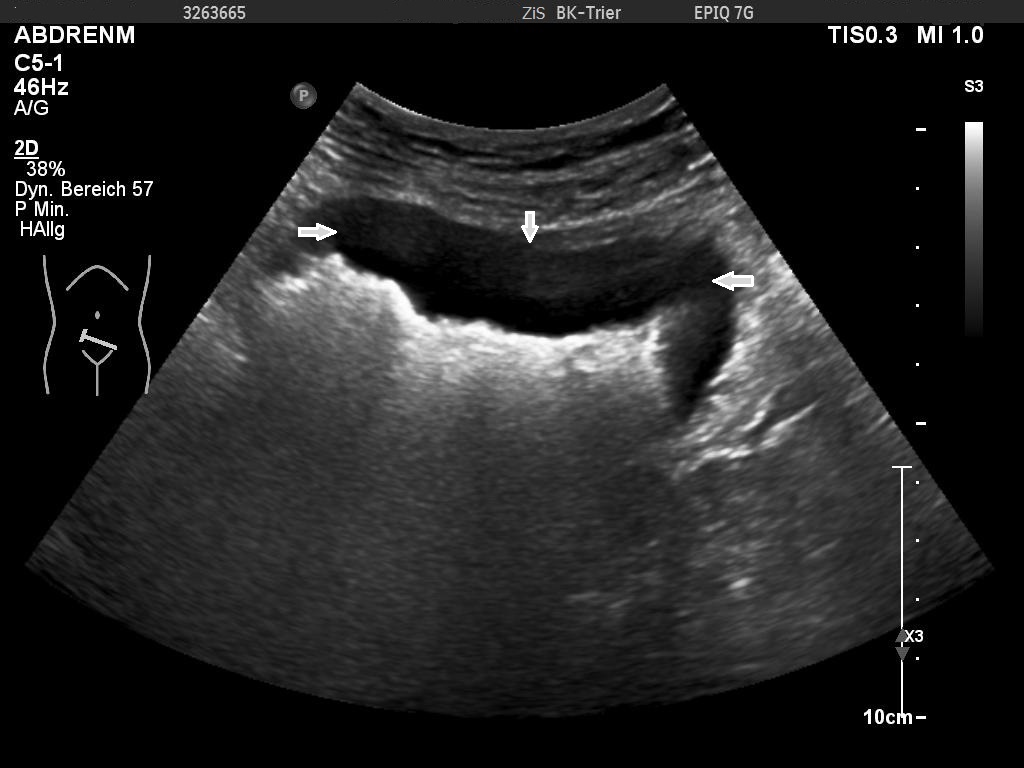

The examination revealed a segment of the ileum with substantial semicircular and homogenous hypoechoic wall thickening over a length of about 10 cm. There was no differentiation of wall layers possible. There was also no intraluminal narrowing of the thick- walled bowel segment or bowel dilatation. Colour Doppler revealed straight vessels within the hypoechoic thickened wall.

Ultrasonographic signs of bowel lymphoma are variable. Circumferential wall thickening is the most common pattern on sonography where a common described feature is of a thickened hypoechoic to anechoic wall with an echogenic centre and is described as a the “target-sign” [7,8]